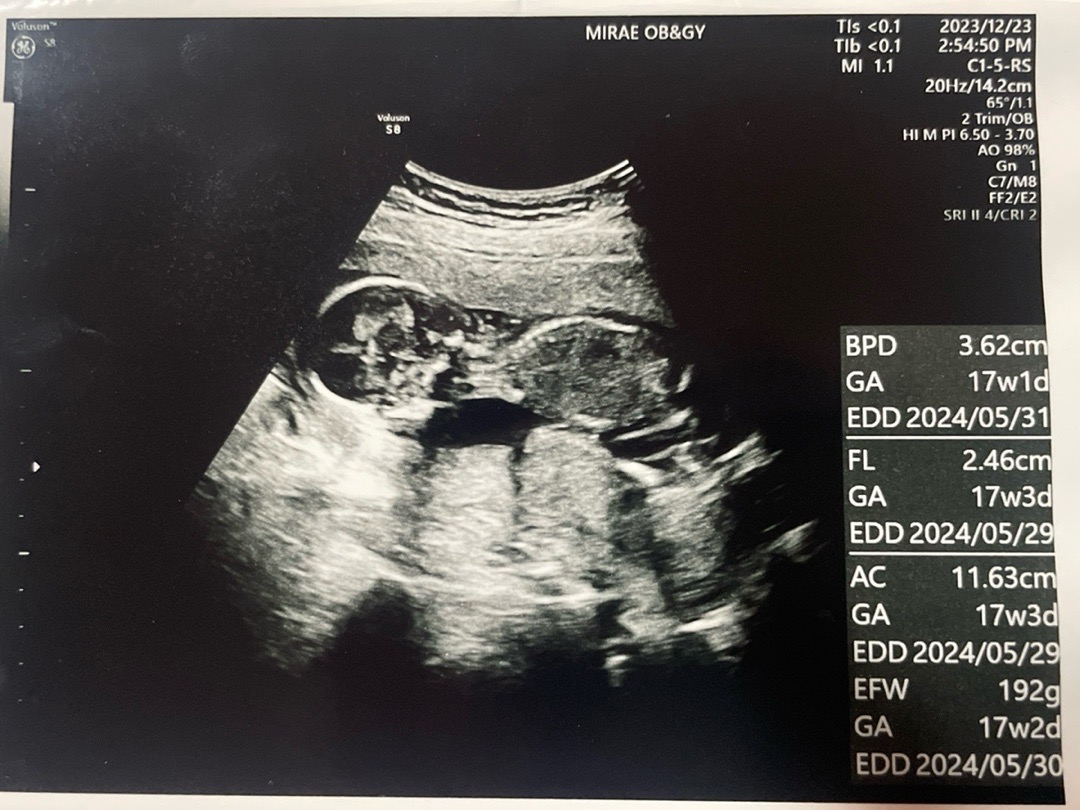

17주 양수부족증상

기형아 1,2차 다 정상인데 아기 성별보러 갔다가 양수가 부족하대요 ㅠㅠ 아기 양수부족 원인을 모르겠다고 하시는데 왜그런걸까요? 양수가 부족하면 아기가 발달이 잘안되거나 할 수 있다는데 저 같은 분 있으신가요?? 선생님이 2L씩 물을 마시라고 하셔서 커피는 임신하고 잘 마시지 않았지만 아주 가끔 먹고싶으면 디카페인 먹었었는데 디카페인도 끊고 포카리랑 물, 루이보스차 엄청 마시고 있어요 ㅜㅜ 너무 걱정되서 3일 뒤에 다시갔더니 물 많이 마시니 조금 늘었다고는 하시는데 왜그런걸까요 제가 평소에 악건성에 물을 잘 안마셔서 그럴까요ㅠ 양수가 부족했어도 물 많이 먹으면 건강한 아기 출산하겠죠?